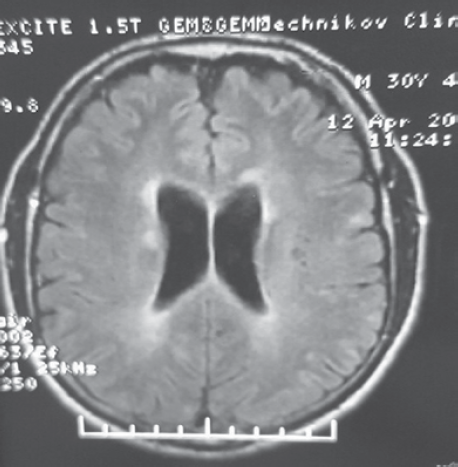

МРТ головного мозга с контрастированием в режимах Т1 и Т2 ВИ. В белом веществе лобных, теменных и левой височной долей с обеих сторон паравентрикулярно и субкортикально, в мозолистом теле, стволе и ножках мозжечка выявляются множественные очаги демиелинизации, имеющие гиперинтенсивный сигнал по Т2, TIRM и изогипоинтенсивный сигнал по Т1.

Без признаков перифокального отека. Общее количество очагов T2/FLAIR — 10–20. В субкортикальных отделах левой лобной доли визуализируется группа кист размером от 0,3 до 0,7 мм в диаметре с минимальной зоной глиоза. Боковые желудочки не расширены, симметричны с умеренно выраженной зоной глиоза по периферии. Умеренная атрофия мозолистого тела. Сразу после введения контрастного вещества выявляется усиление сигнала по типу кольца от единичных очагов в правой лобной доле.

Заключение: «Картина демиелинизирующего поражения головного мозга.

Зона кистозных изменений в субкортикальных отделах левой лобной доли» (рис. 1 и 2).

Рис. 1. МРТ Т2 ВИ больного З. Перивентрикулярная демиелинизация, вентрикулярная дилатация и конвекситальная атрофия мозга